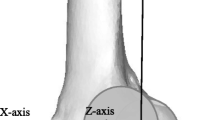

The 3D models were imported in software designed to model three-dimensional geometries and subject-specific reference systems implementation (nmsBuilder v2.0, Rizzoli Orthopaedic Institute, Bologna) [27]. This software allows creating an anatomical reference system on tibia and femur 3D models according to ISB recommendation [28]. The 3D position of the tibia and femur at the moment BB was reconstructed in nmsBuilder: through the “Transform” operation command, BB was matched based on the maximal possible congruency between their external surfaces (Fig. 2). Three different investigators (P.A., A.G., and S.D.P.) reviewed the results. Finally, the software output describing the position and orientation of the tibia referred to the femur at BB was obtained.

Example of 3D models positioning matching BB areas in nmsBuilder [27]: lateral view (a) and 45° frontal view (b)